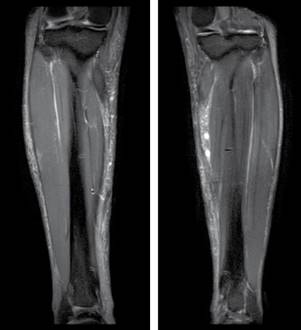

En el estudio de resonancia magnética (RM) de piernas se identificó edema de tejidos blandos superficiales de ambas piernas con depósitos de material modelante en la porción superior del músculo gemelo medial de la pierna derecha y en la pierna izquierda se observa material modelante en toda su longitud sin compromiso de los planos musculares (Figura 3).